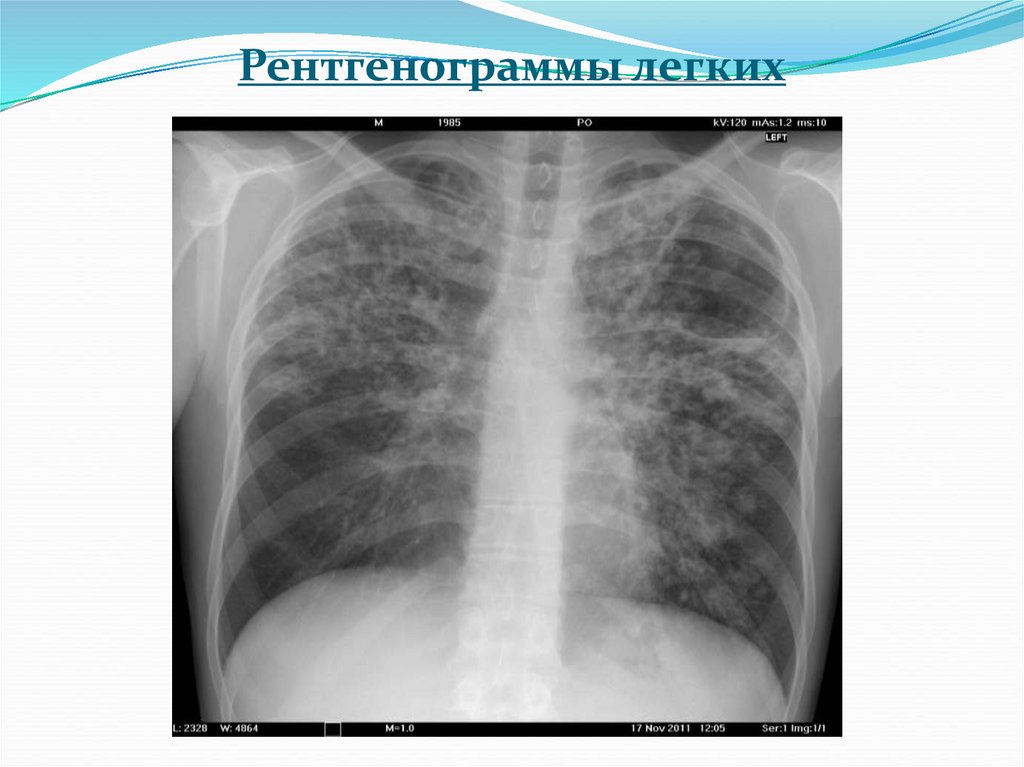

6. Рентгенограммы легких